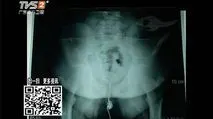

原创男孩蛋疼3天睾丸被切除妈妈的一个疏忽毁了孩子的终身性福